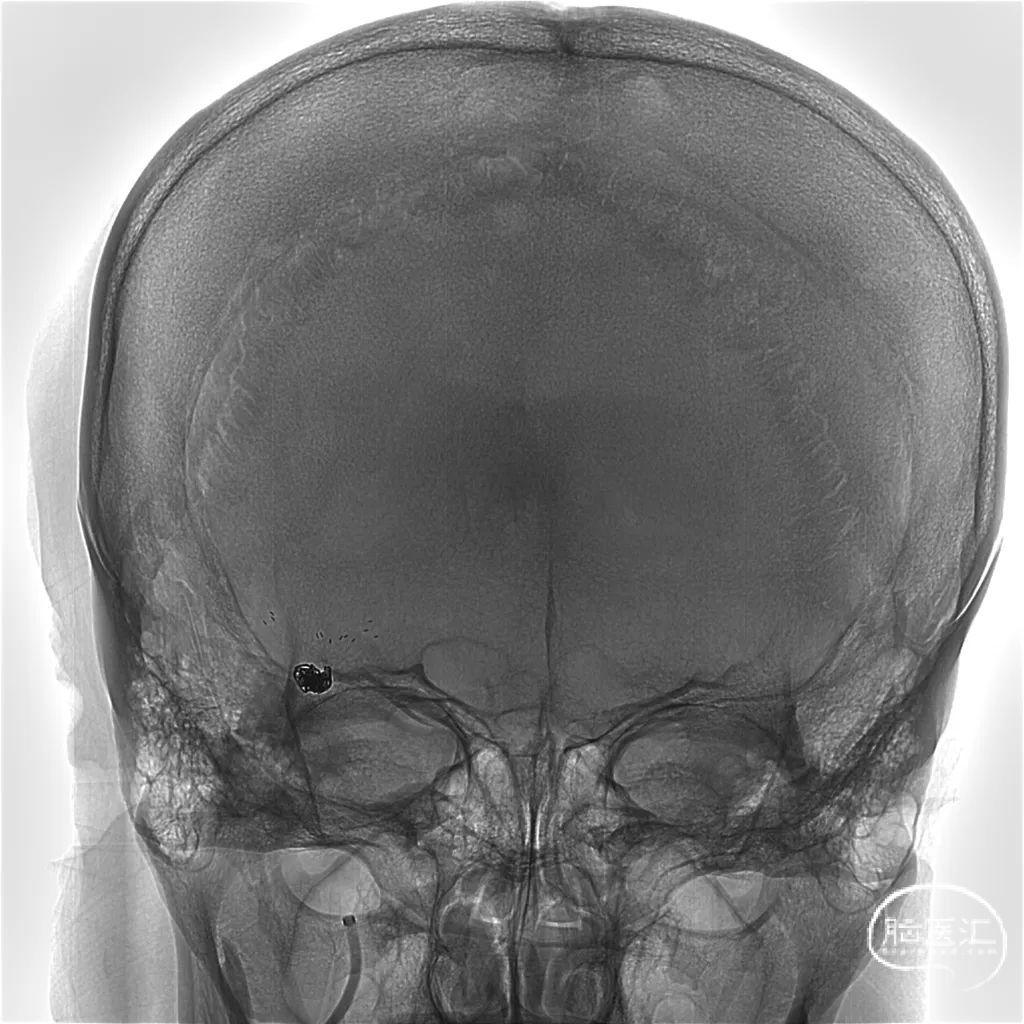

术后即刻正位造影及蒙片:造影显示瘤体致密栓塞,支架贴壁和导流良好。